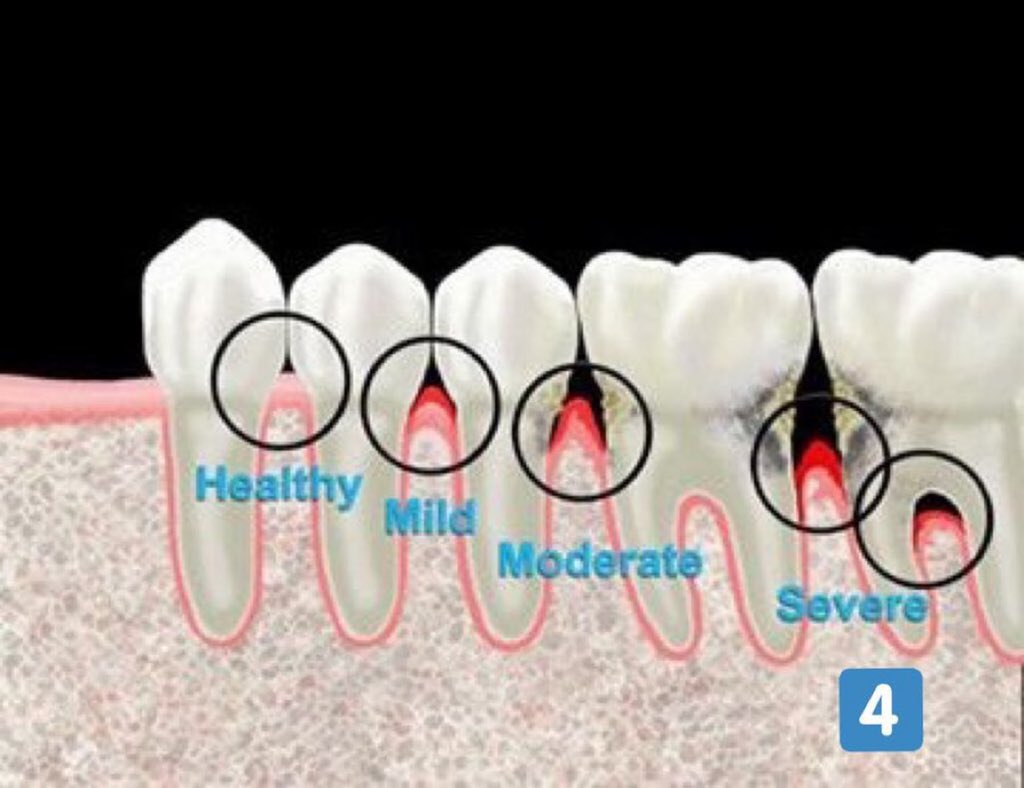

مراحل التهاب اللثة:

التهاب اللثة الخارجي(مرحلة١):

-الإنتفاخ

-الإحمرار

-النزف

-الألم

-سهل العلاج ويختفي تماماً

التهاب اللثة العميق(مرحلة٢):

-تآكل بسيط في اطراف العظم الداعم للآسنان وقد(غالبا)يكون مصحوب بعلامات من التهاب اللثة الخارجي

-يمكن علاجه إذا اكتشف باكرا وإيقاف تقدمه.(٣)=

-التهاب اللثة العميق (متوسط) (المرحلة ٣):

- بعض علامات التهاب اللثة الخارجية (ليس بالضرورة تكون موجودة)

-تآكل لمستوى اكثر في العظم الداعم

-نزوح في اللثة الخارجية (النسيج المحيط بالأسنان) (أحيانا)

-بدء حركة الأسنان بدرجة بسيطة

-يكتشف احيانا بالصدفة عند اخذ أشعة الأسنان(٤)=

لمرحلة المتقدمة من التهاب اللثة (المرحلة ٤):

-ألم ونزف

-حركة واضحة ومؤلمة عند المضغ

-رائحة كريهة ومزعجة

-سقوط الأسنان بدون التعرض لضربات أو حوادث

-العلاج قد يكون غير ممكن 💔 (٥)=